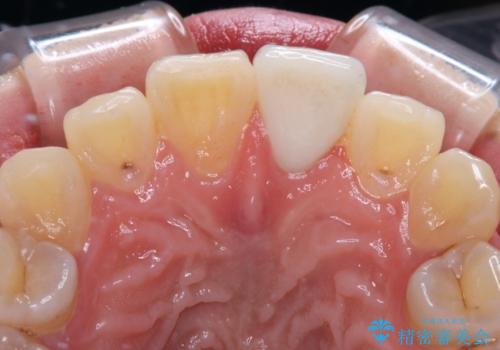

- ぶつけて欠けてしまった前歯を樹脂でつめていたものの、すり減りや変色が顕著とのことで来院された患者様です。

詰め物の詰め直しとオールセラミッククラウンの双方をご提案し、患者様ご希望によりオールセラミッククラウンにて補綴治療を行うこととしました。

歯列全体に表面の着色があったため、クリーニングとホワイトニングを事前に行い、ホワイトニング後1ヶ月ほどおいて、色の落ち着いたところで色合わせを行いました。